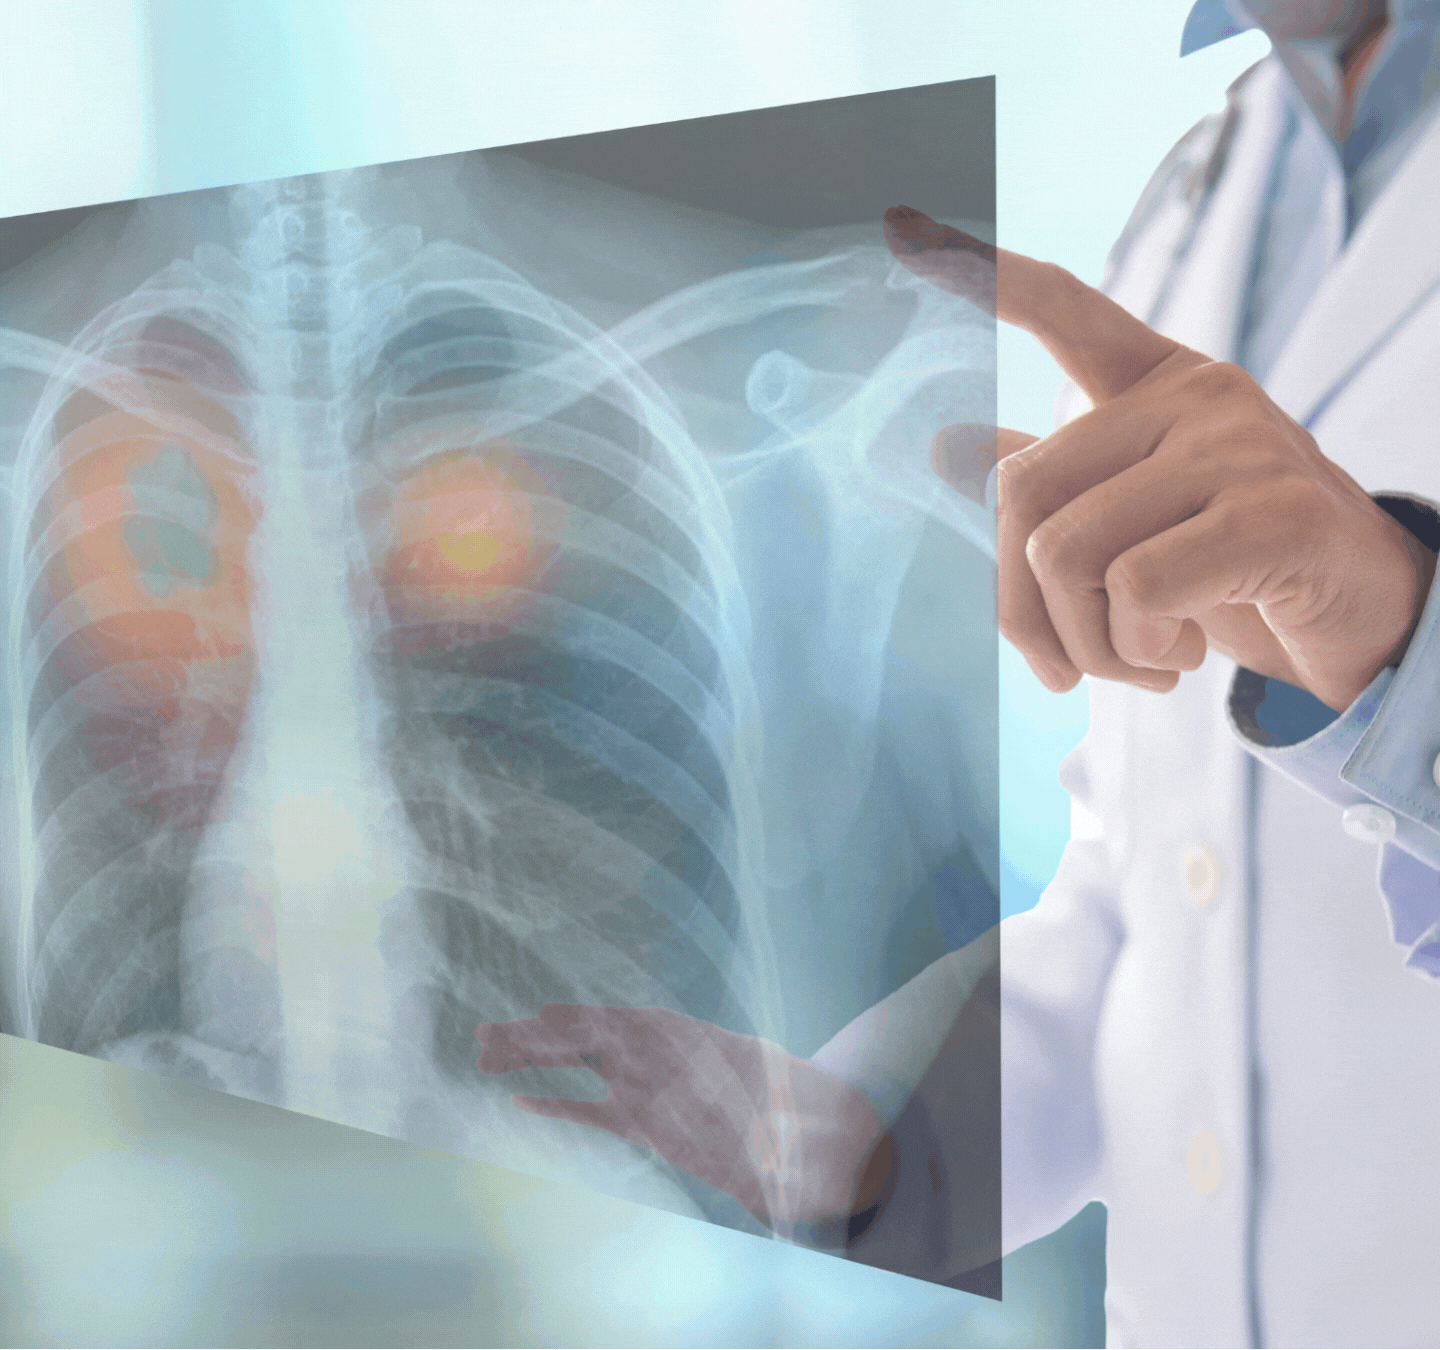

ศูนย์อัลตราซาวนด์และรังสีวินิจฉัย โรงพยาบาลจักษุสุราษฎร์ ให้บริการตรวจวินิจฉัยหาสาเหตุของโรคด้วยการถ่ายภาพรังสี ครอบคลุมการตรวจทางรังสีทั่วไป (Digital Radiography) และการตรวจพิเศษต่าง ๆ ด้วยเครื่องมือทางรังสีวิทยาที่มีคุณภาพด้วยวิธีการที่ได้มาตรฐาน ถูกต้อง และแม่นยำ ภายใต้การดูแลของรังสีแพทย์และบุคลากรทางการแพทย์ที่มีความสามารถ เพื่อให้ได้ภาพที่สามารถใช้ในการวินิจฉัยและรักษาโรค รวมทั้งปลอดภัยต่อผู้รับบริการ โดยเทคโนโลยีระบบจัดการข้อมูลภาพรังสีดิจิตอล PACS (Picture Archiving and Communication System) โดยมีขอบเขตการบริการดังนี้

• การตรวจวินิจฉัยด้วยเครื่องเอ็กซเรย์ระบบดิจิตอล (Digital Radiography)

• การเอ็กซเรย์ปอด